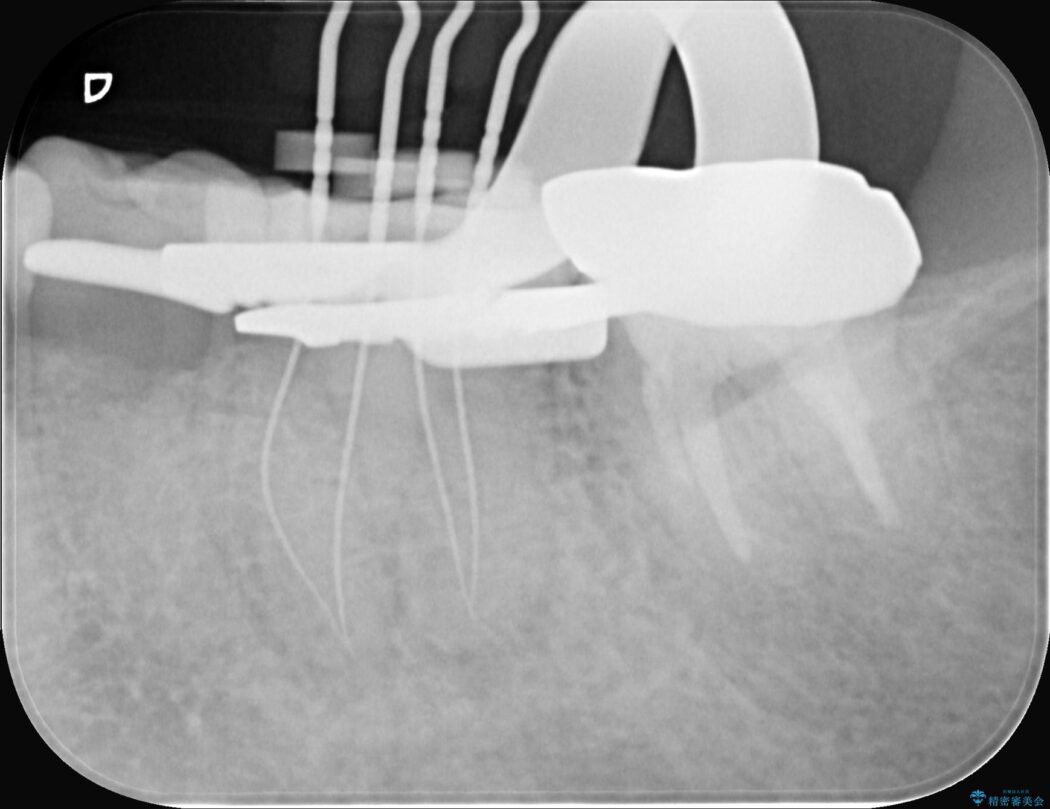

まず、治療中の細菌感染を防ぐためにラバーダムを使用。次に、歯科用顕微鏡で治療部位を何十倍にも拡大しながら、狭窄した根管の入り口を探し、慎重に拡大・清掃を行いました。顕微鏡を用いることで、肉眼では不可能だった根管内部の細かい構造を確認しながら、感染源を徹底的に除去することができました。これにより、難症例の奥歯でも再発リスクを抑えた適切な処置を行うことができ、治療後に痛みは解消。大切な歯を長期間にわたり保存することができました。